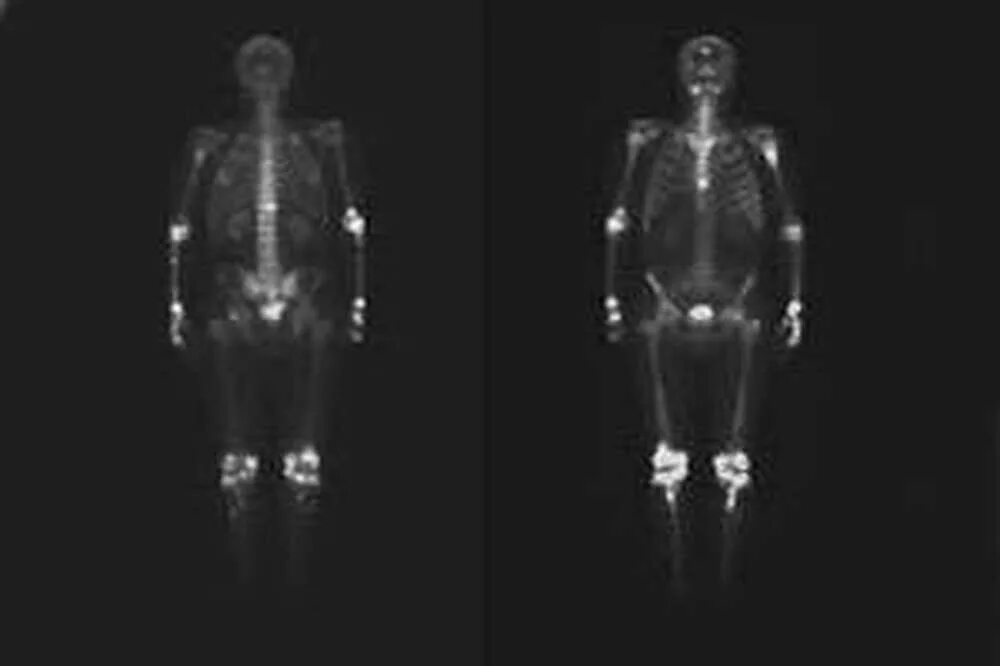

Метастазы скелета